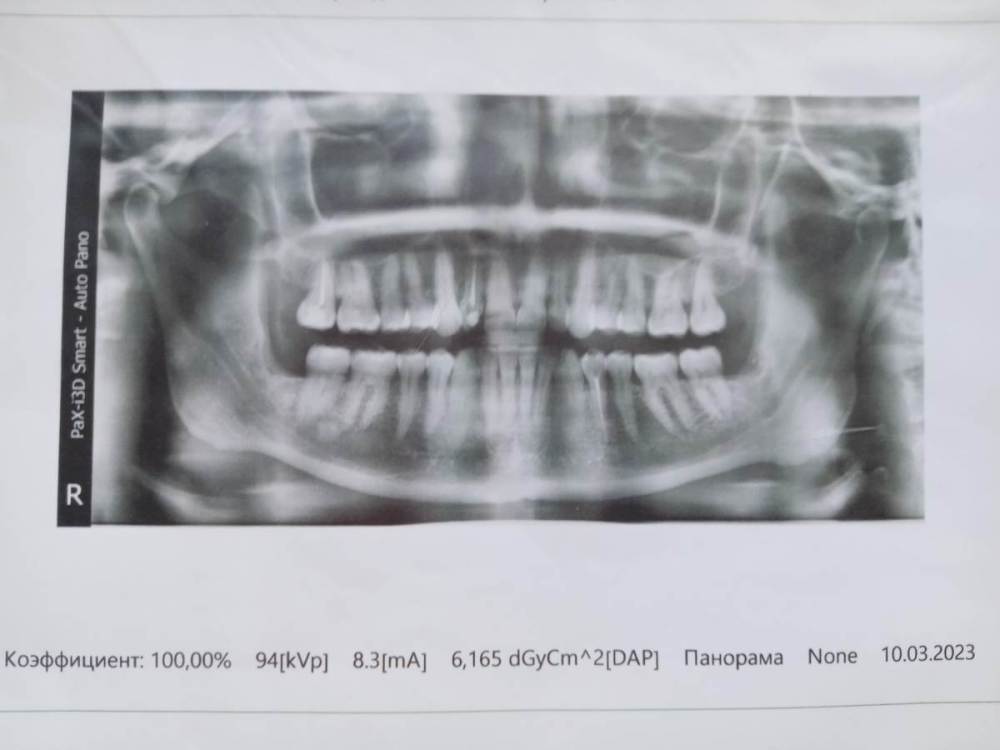

Irouil Опубликовано 29 июня, 2023 Поделиться Опубликовано 29 июня, 2023 Сделайте свежий снимок 1 Ссылка на комментарий

СмирноваД Опубликовано 29 июня, 2023 Автор Поделиться Опубликовано 29 июня, 2023 16 минут назад, Irouil сказал: Сделайте свежий снимок Вот. Март 2023 1 Ссылка на комментарий